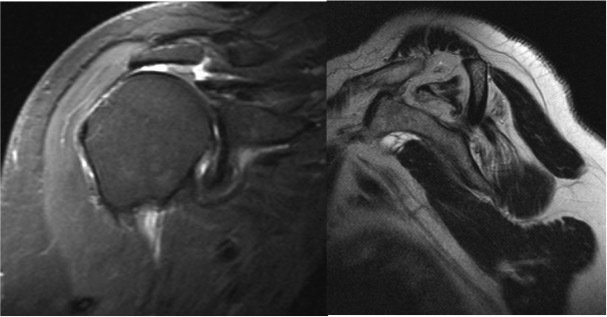

The procedure is performed to treat a symptomatic rotator cuff tear of the shoulder.

The procedure is performed under a combination of general and regional anaesthesia. Most rotator cuff repairs are performed arthroscopically but repair of some large tears may be carried out through an “open” procedure. The inside of the joint and subacromial bursa are examined. A small amount of bone is removed from the undersurface of the acromion. The bone where the tendon normally attaches is freshened to promote bleeding and facilitate healing. The tendon is then fixed back to bone with suture anchors.

Other procedures such as an acromioclavicular joint excision, biceps tenotomy or tenodesis, labral repair or capsular release may be performed, if indicated, at the same time. If the tear is very big or if the tendon quality is poor, the repair may be reinforced with a “patch” of donor tissue. If the tear is found to be irreparable, a superior capsular reconstruction may be performed.